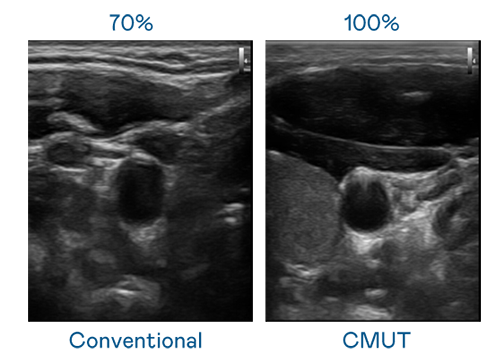

CMUT 技术是一种用电容式微机电元件来产生超音波讯号的技术。与传统 PZT 压电式技术相比,CMUT 频宽增加 30%,更宽频的超音波讯号让影像解析度大幅提升,是实现高影像品质医疗超音波扫描、促进精准医疗发展的关键技术。

超音波影像的解析度高低,首先取决于探头能发出的讯号频宽。永利 CMUT 可提供高清晰的超音波讯号,提供高频宽、高灵敏度、影像纹理细节更高的超音波影像,协助医护人员缩短影像判读时间及利用精准的医疗影像进行诊断。